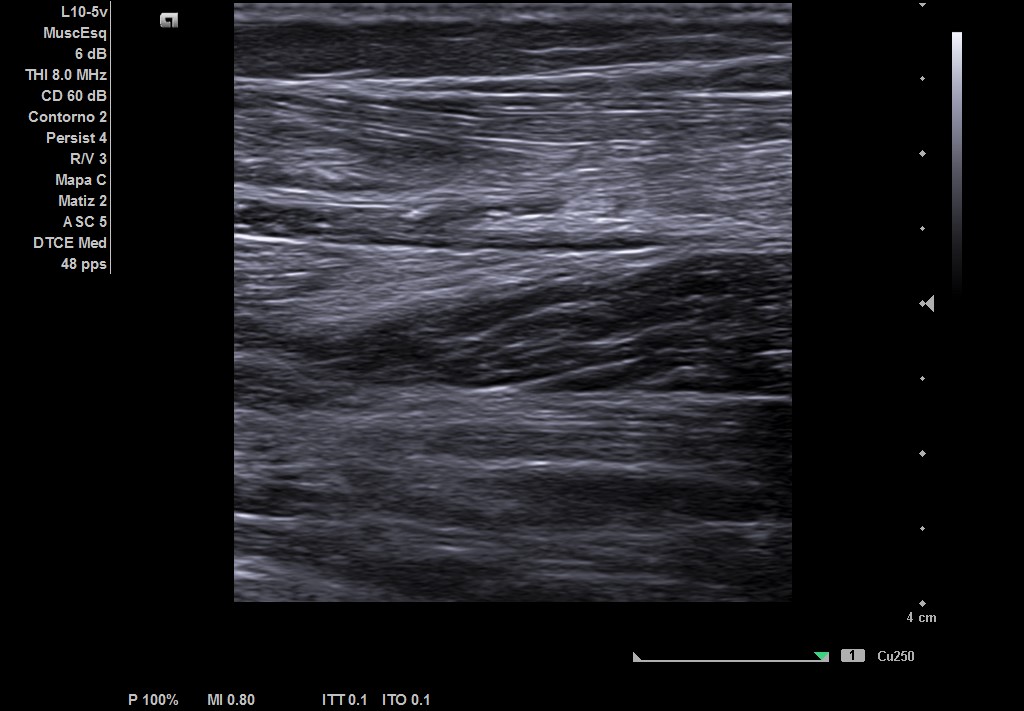

Descripción de los hallazgos ecográficos y las imágenes más relevantes para la resolución del caso

Ecografía musculoesqueletica: se objetiva signos de rotura de inserción gemeral interno-soleo de 21 x 32 mm y línea de líquido en zona superior intergastronemios de 1 mm de grosor. Doppler negativo.

Estamos ante una rotura fibrilar grado II según dicha clasificación.

Si correlacionamos la clínica, clasificación ecográfica y pronóstico. Nos encontramos con un grado II: Rotura Fibrilar. Pronóstico de 3 a 8 semanas.